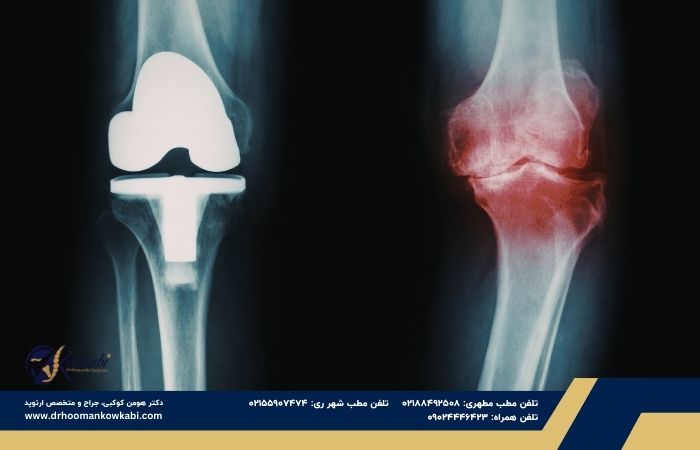

تعویض مفصل زانو یکی از موفقترین جراحیهای ارتوپدی در جهان است، اما با وجود آمارهای امیدوارکننده، هنوز هم برای بسیاری از بیماران با ترس، نگرانی و سوالهای جدی همراه است.

واقعیت این است که تعویض مفصل زانو یک جراحی بزرگ محسوب میشود، اما در عین حال یکی از ایمنترین و استانداردترین جراحیهای ارتوپدی در دنیا است. امروزه با پیشرفت تکنیکهای جراحی، بیهوشی مدرن و کنترل دقیق شرایط بیمار قبل از عمل، میزان عوارض به شکل قابلتوجهی کاهش یافته است.

مطالعات بینالمللی نشان میدهد که بیش از ۹۰ تا ۹۵ درصد بیماران پس از تعویض مفصل زانو، کاهش چشمگیر درد و بهبود عملکرد حرکتی را تجربه میکنند. همچنین طول عمر مفصل مصنوعی معمولاً بین ۱۵ تا ۲۰ سال و حتی بیشتر است.

تعویض مفصل زانو عمل خطرناکی محسوب نمیشود، بلکه یکی از موفقترین جراحیهای ارتوپدی است که میتواند درد مزمن و ناتوانکننده را برطرف کند.